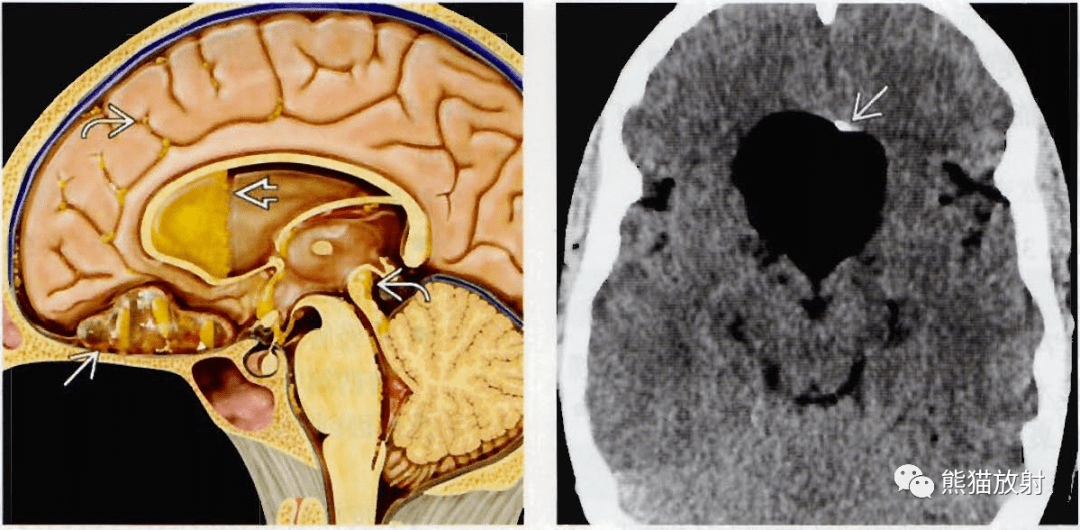

松果体区表皮样囊肿1例

第四脑室表皮样囊肿一例